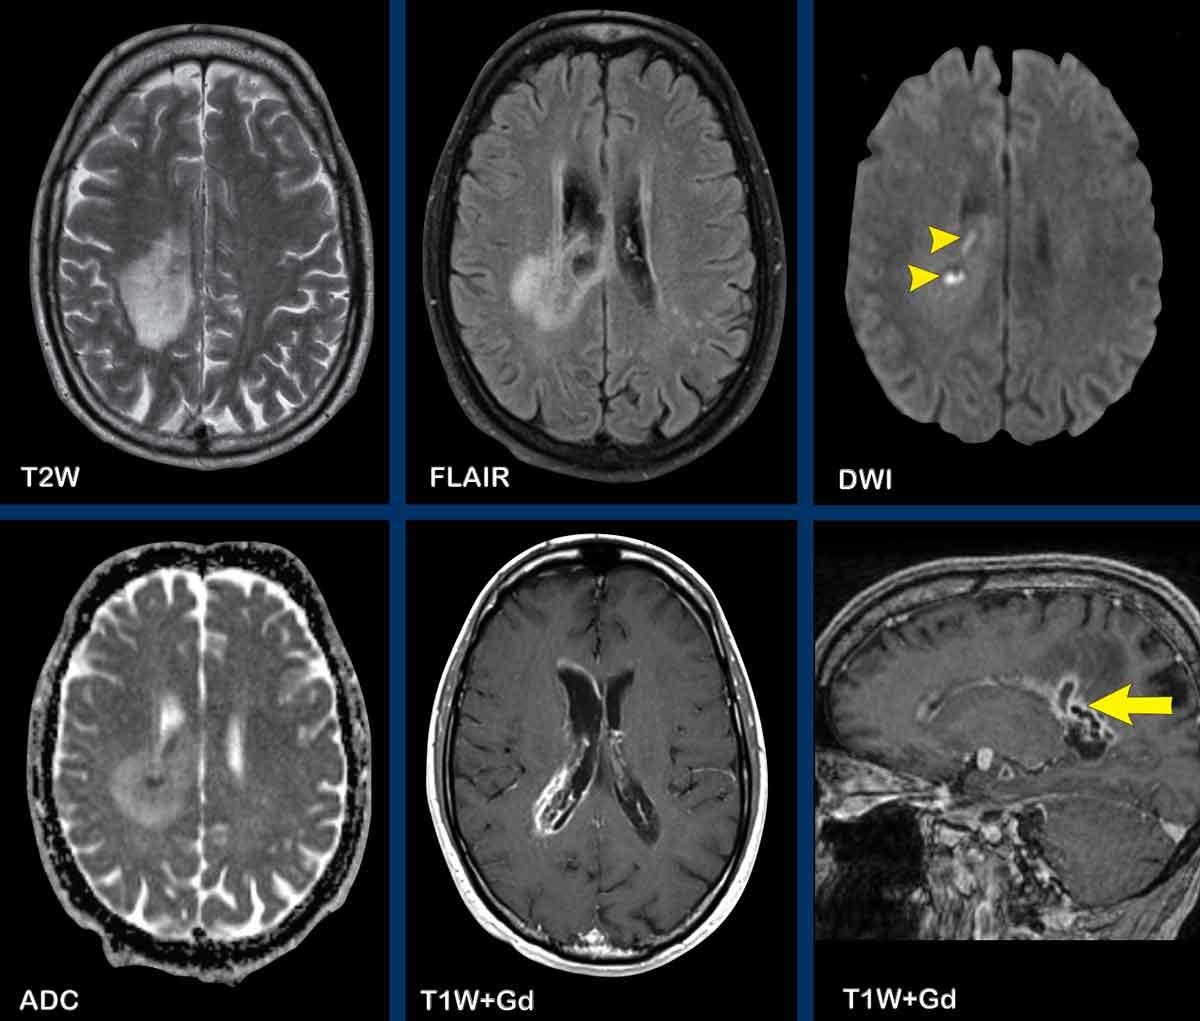

U lympho

Các hình ảnh này của một phụ nữ 76 tuổi, có biểu hiện lú lẫn sau khi ngã.

Hãy quan sát các hình ảnh trước rồi mới tiếp tục đọc.

Câu hỏi:

- Chẩn đoán có khả năng nhất là gì?

- Những dấu hiệu nào điển hình cho chẩn đoán này?

Các dấu hiệu bao gồm:

- Tổn thương tăng tỷ trọng trên CT không tiêm thuốc cản quang kèm phù não do mạch máu.

- MRI cho thấy nhiều tổn thương ngấm thuốc dạng đặc và hạn chế khuếch tán.

- Trên chuỗi xung T2W, các tổn thương biểu hiện giảm tín hiệu.

- Một tổn thương nằm ở thể chai và một tổn thương khác nằm cạnh não thất.

Tất cả các dấu hiệu này đều điển hình cho u lympho nguyên phát hệ thần kinh trung ương, khác với u lympho hệ thống.

Các khối u này chiếm 6-7% tổng số u hệ thần kinh trung ương và mô học là u lympho tế bào B không Hodgkin.

Chúng thường nằm ở vùng cạnh não thất dưới màng nội tủy, thể chai và hạch nền.

Luôn nghĩ đến u lympho khi gặp tổn thương ngấm thuốc dạng đặc nằm gần não thất.

Hình ảnh tăng tỷ trọng trên CT, giảm tín hiệu nhẹ trên chuỗi xung T2W cũng như hạn chế khuếch tán được giải thích là do mật độ tế bào dày đặc của mô u lympho.

Ở bệnh nhân suy giảm miễn dịch, kiểu ngấm thuốc có thể là dạng vòng nhẫn.

Bệnh nhân này có nhiều phù não, nhưng trong nhiều trường hợp phù não rất hạn chế.